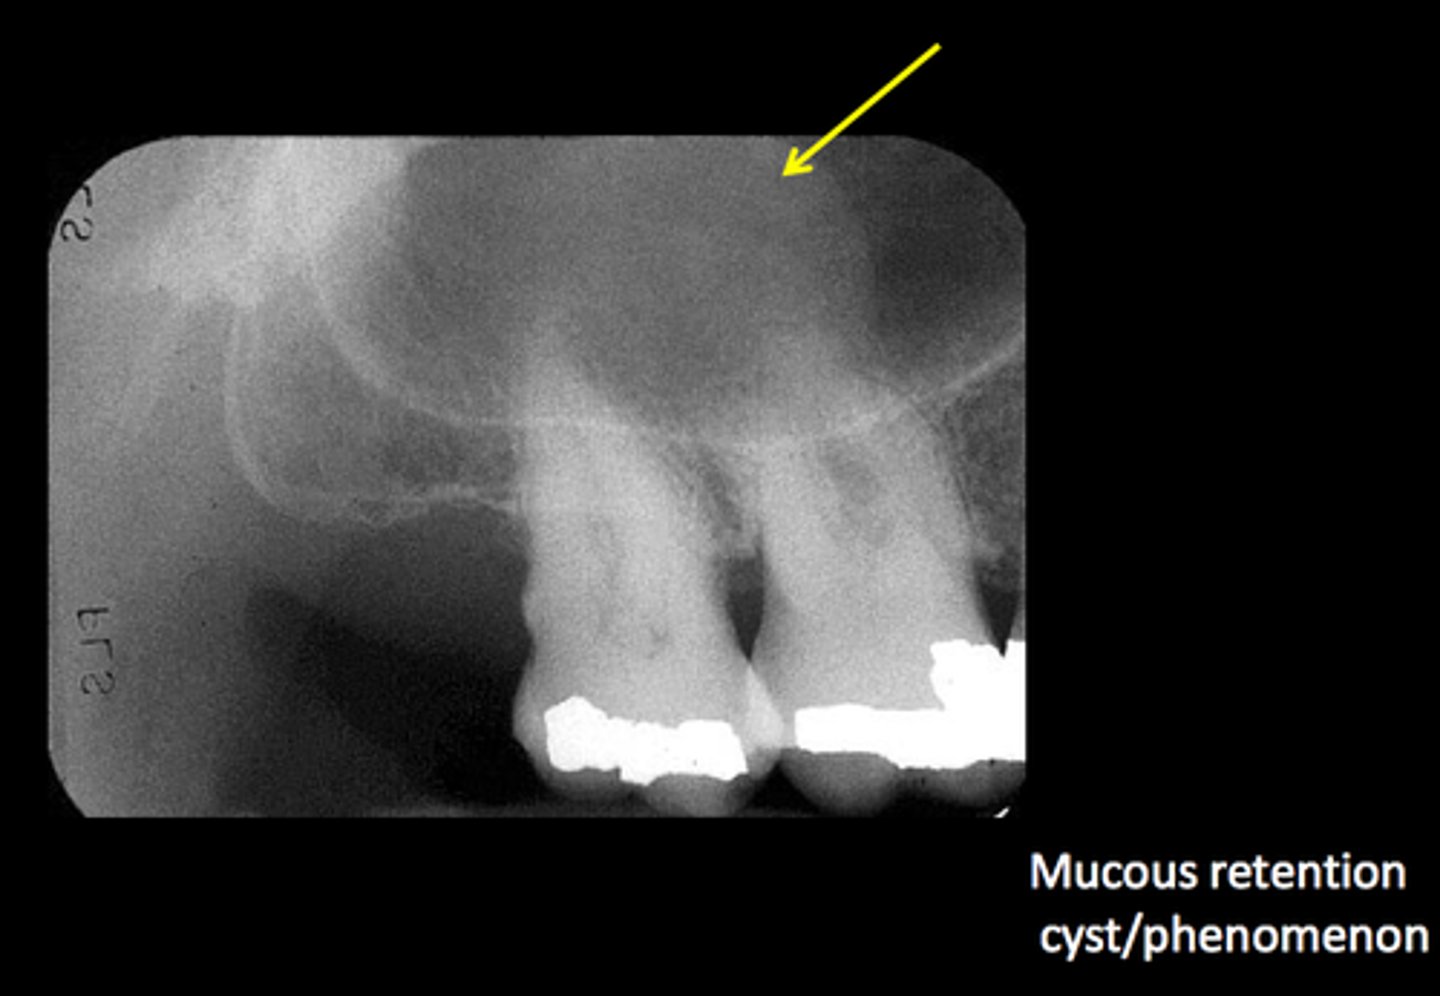

Radiopacity on a pan. What is it?

Mucous retention cyst in the maxillary sinus